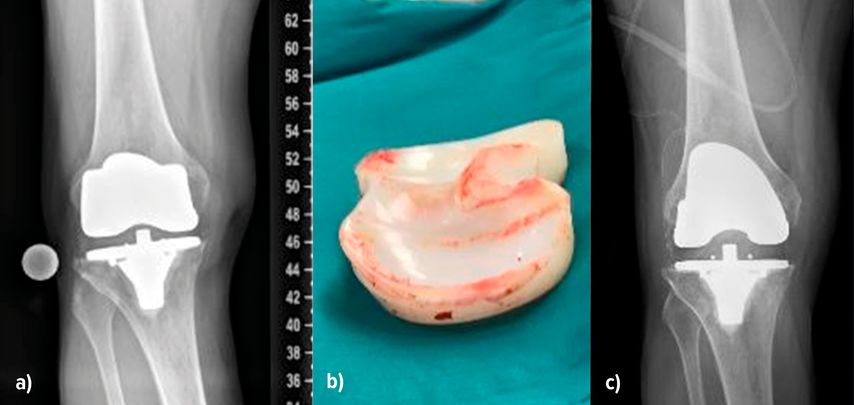

Abb. 1:Instabilität infolge eines Verschleisses. Im ap. Röntgenbild (a) sind die vermehrte laterale Aufklappbarkeit und die mediale Verschmälerung des Gelenkspaltes gut sichtbar. Das Inlay weist deutliche Verschleissspuren auf (b). Nach dem Wechsel auf ein neues Inlay in primärer Höhe ist im Röntgenbild der Gelenkspalt wieder gleichmässig dargestellt (c)